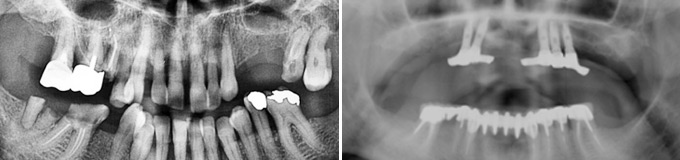

Il me manque de nombreuses dents, les autres sont perdues, je veux l’idéal.

Solution : on peut remplacer toutes vos racines manquantes ou perdues par autant de racines artificielles et vous redonner des dents fixes partout.

Toutes dents sont hélas perdues. Toutes les dents absentes sont remplacées par des couronnes sur implants.